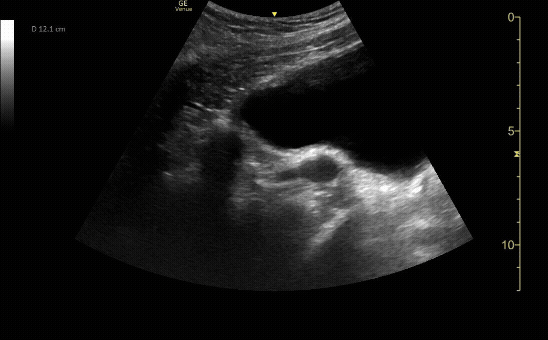

Transverse view of the uterus with molar pregnancy.

c/o Ramin Chitsaz, MD